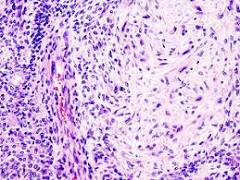

restoration hardware goldenrod curtains Histologically, it is highly variable in appearance, even within individual tumors.

net curtain wire b&qClassically it is biphasic and is characterized by an admixture of polygonal epithelial and spindle-shaped myoepithelial elements in a variable background stroma that may be mucoid, myxoid, cartilaginous or hyaline.

Epithelial elements may be arranged in duct-like structures, sheets, clumps and/or interlacing strands and consist of polygonal, spindle or stellate-shaped cells (hence pleiomorphism). Areas of squamous metaplasia and epithelial pearls may be present. The tumor is not enveloped, but it is surrounded by a fibrous pseudocapsule of varying thickness. The tumor extends through normal glandular parenchyma in the form of finger-like pseudopodia, but this is not a sign of malignant transformation.